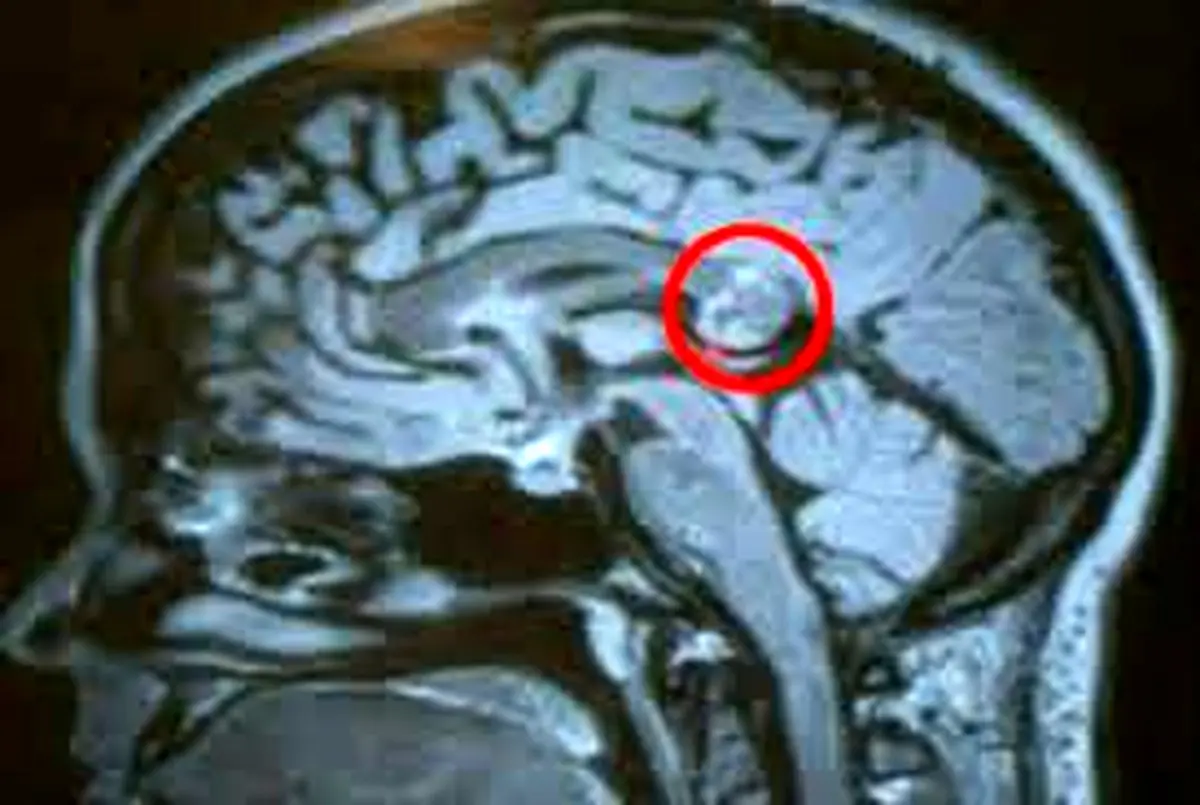

نشانه های هشداردهنده تومور مغزی

علائم سرطان مغز بینهایت شبیه سایر بیماری‌های معمولی هستند، از سردرد‌ها گرفته تا افسردگی. در این مطلب به شما می‌گوییم چه زمانی باید به پزشک مراجعه کنید.

خوشبختانه سرطان مغز کمتر از یک درصد افراد را دچار خود می‌کند و متاسفانه تومور‌های مغزی اغلب علائم بسیار کمی دارند. این علائم خود را به صورت بیماری‌های عادی روزمره مانند سر درد و احساس خستگی بروز می‌دهند.